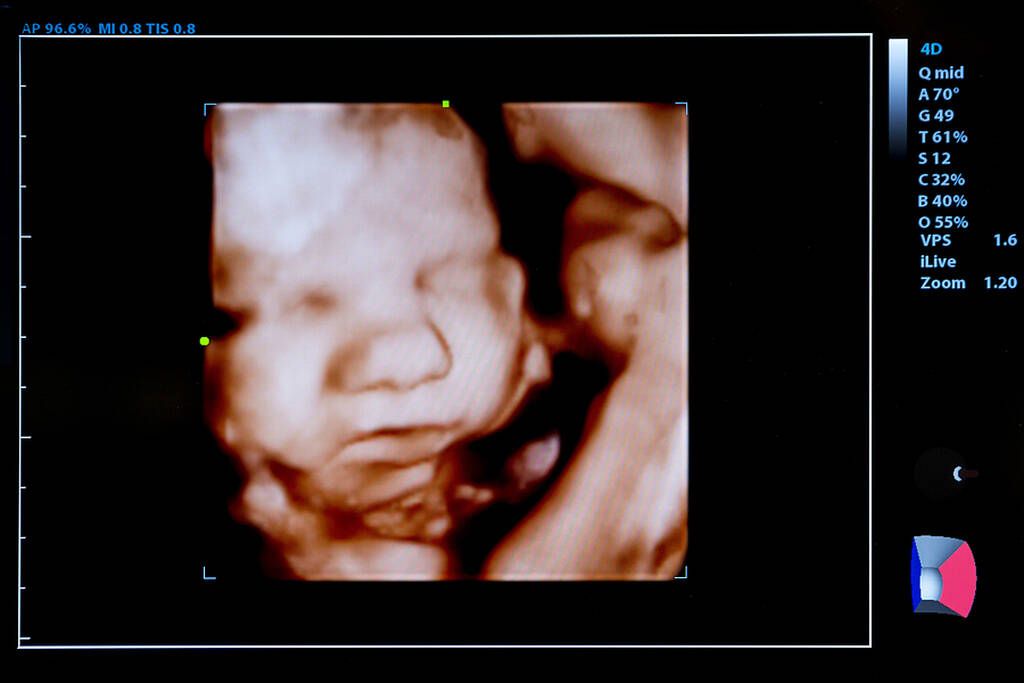

Όλα όσα μαθαίνουν τα μωρά μέσα στην μήτρα

Γνωρίζατε ότι τα μωρά μαθαίνουν κάποια πράγματα μέσα από την μήτρα και πριν ακόμη γεννηθούν;

Από τη στιγμή της γέννησης, ένα βρέφος αρχίζει να απορροφά γρήγορα πληροφορίες, δημιουργώντας σιγά σιγά τον μελλοντικό του εαυτό. Τι συμβαίνει όμως όλο αυτό το διάστημα που το μωρό σας είναι μέσα στην μήτρα; Μαθαίνει πράγματα ενδομήτρια ή όχι;